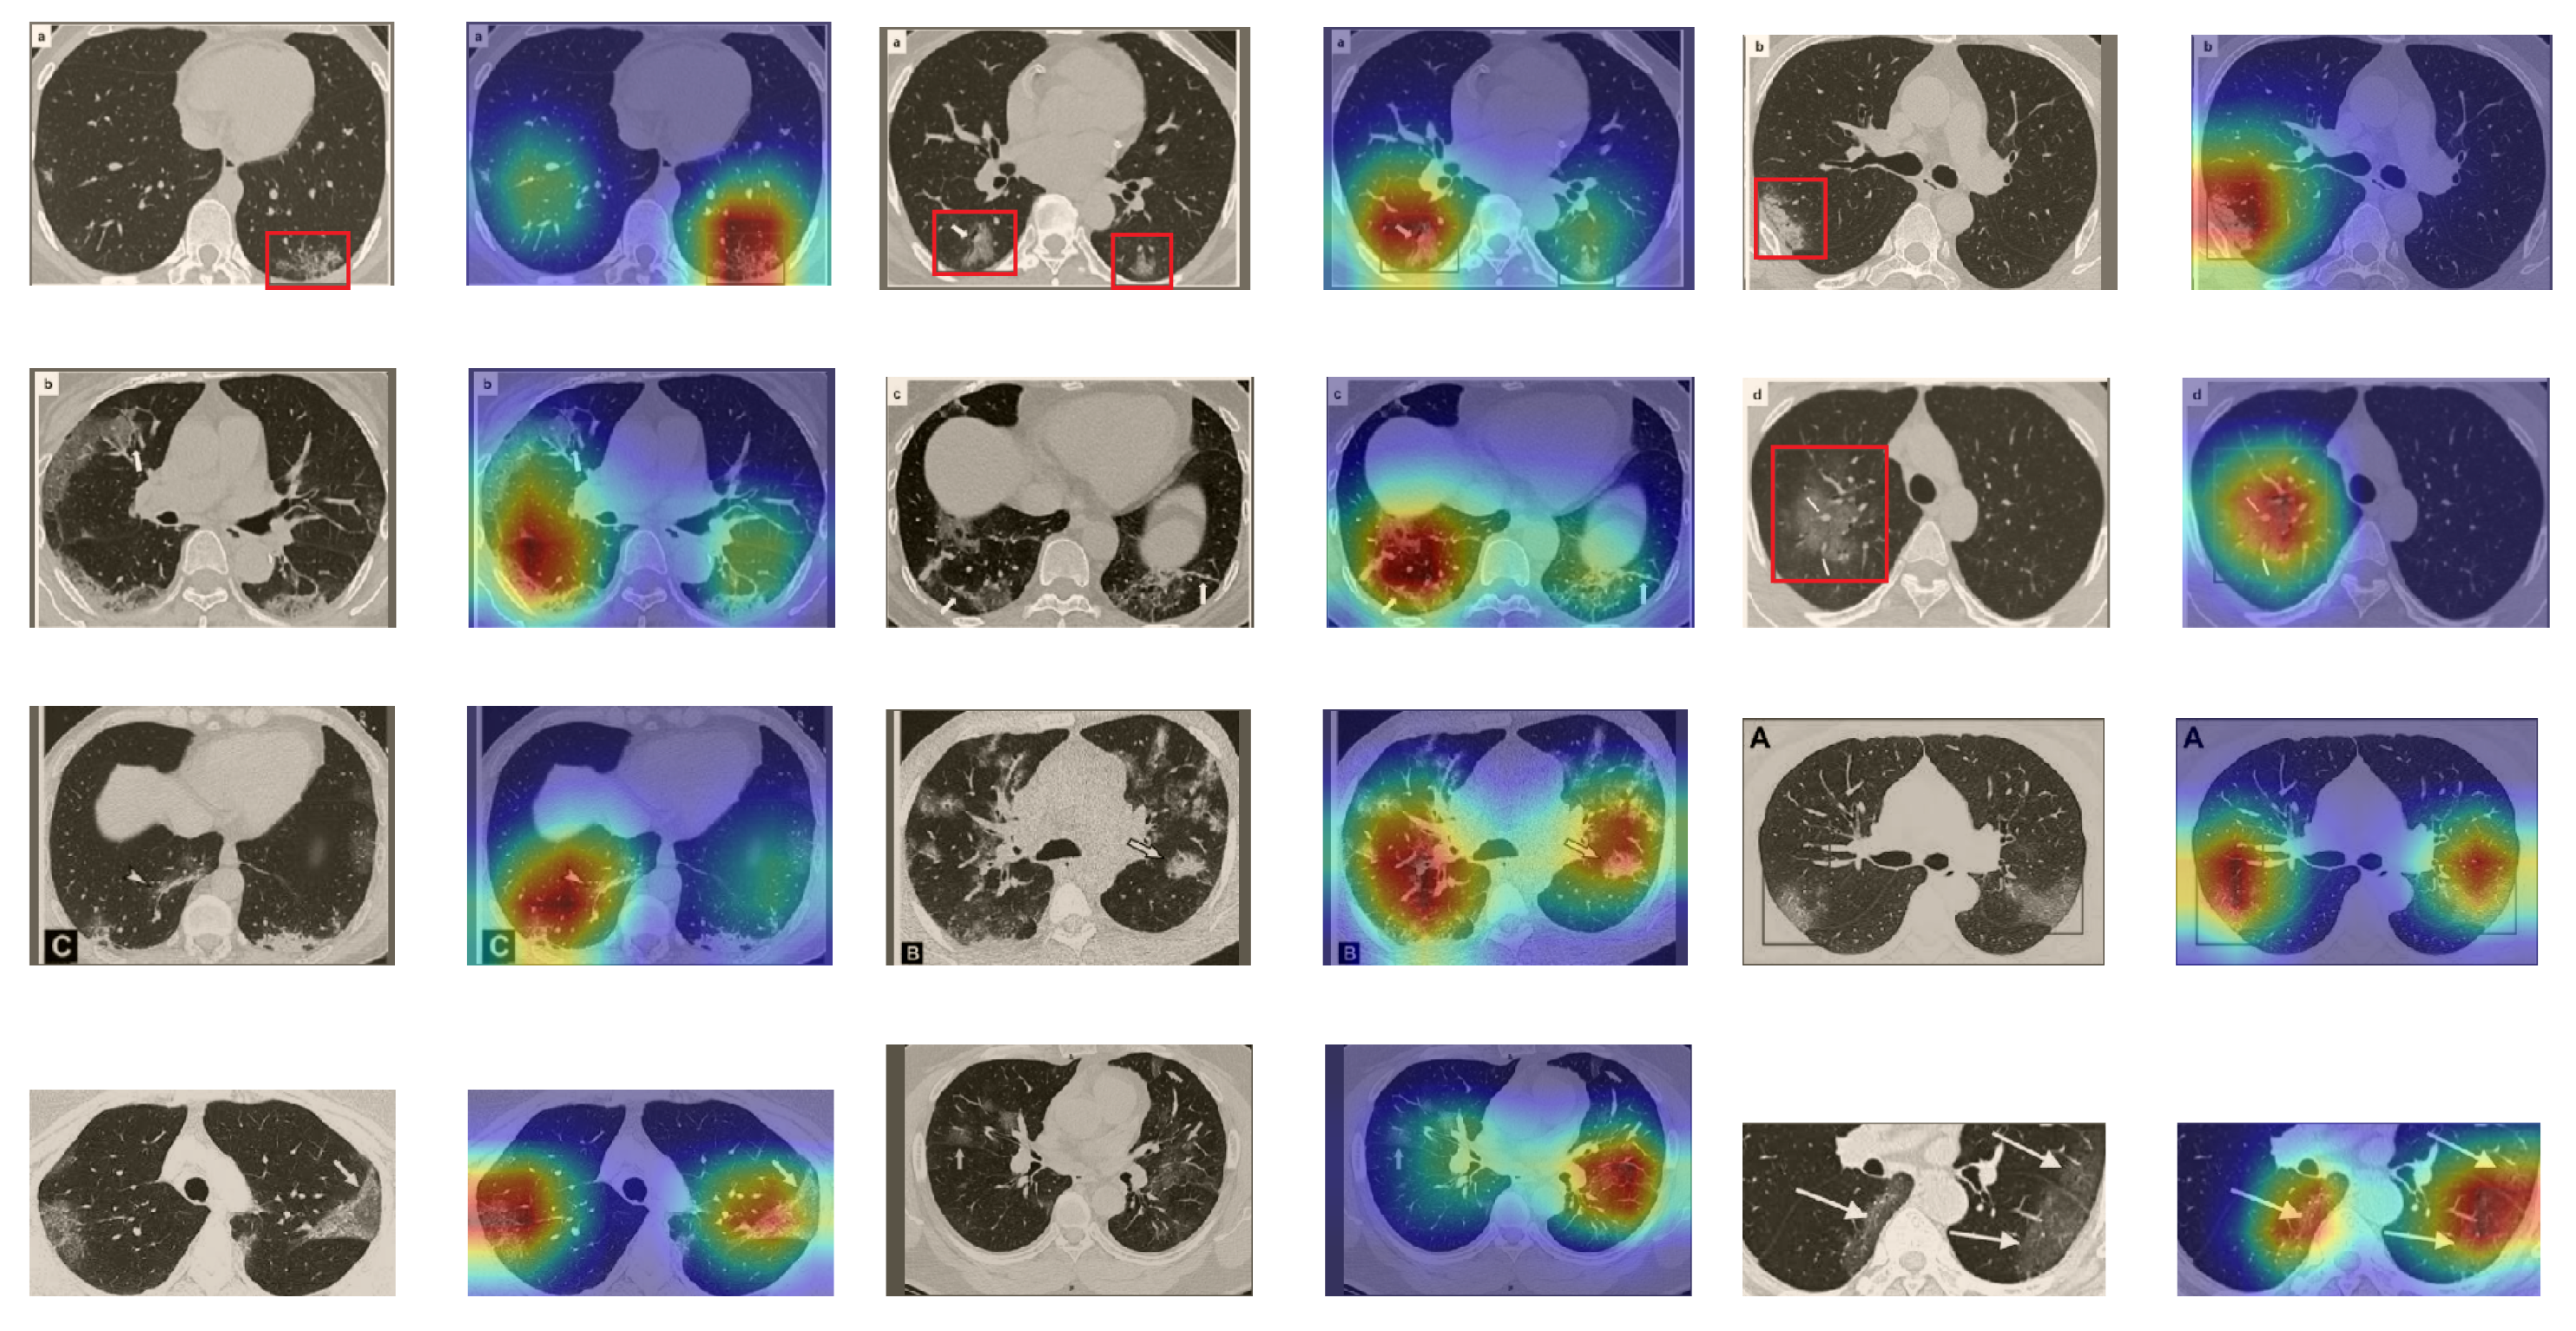

5.5.2. The Grad-CAM Visualization

In order to make our models more transparent and visually interpret the results, we provide the Grad-CAM localization maps generated by using different models. We utilized the CT images from COVID-19 class from the test set for each dataset, and highlight the important regions considered for the prediction. Figure 13 shows examples of CT images from the SARS-CoV-2 CT dataset and their localization maps. Interestingly, in most of the cases, our InceptionV3 model correctly classified them as COVID-19 cases and highlighted the regions of abnormalities in the CT scans, which are important for the model’s decision.

Figure 13.

Grad-CAM visualizations for examples of CT images from the SARS-CoV-2 dataset. Our InceptionV3 model correctly classified them as COVID-19 and localized the most relevant regions used for its decision. The first, third, and fifth columns show CT images with COVID-19 findings, whereas the second, fourth, and sixth columns represent their corresponding localization maps generated by Grad-CAM.